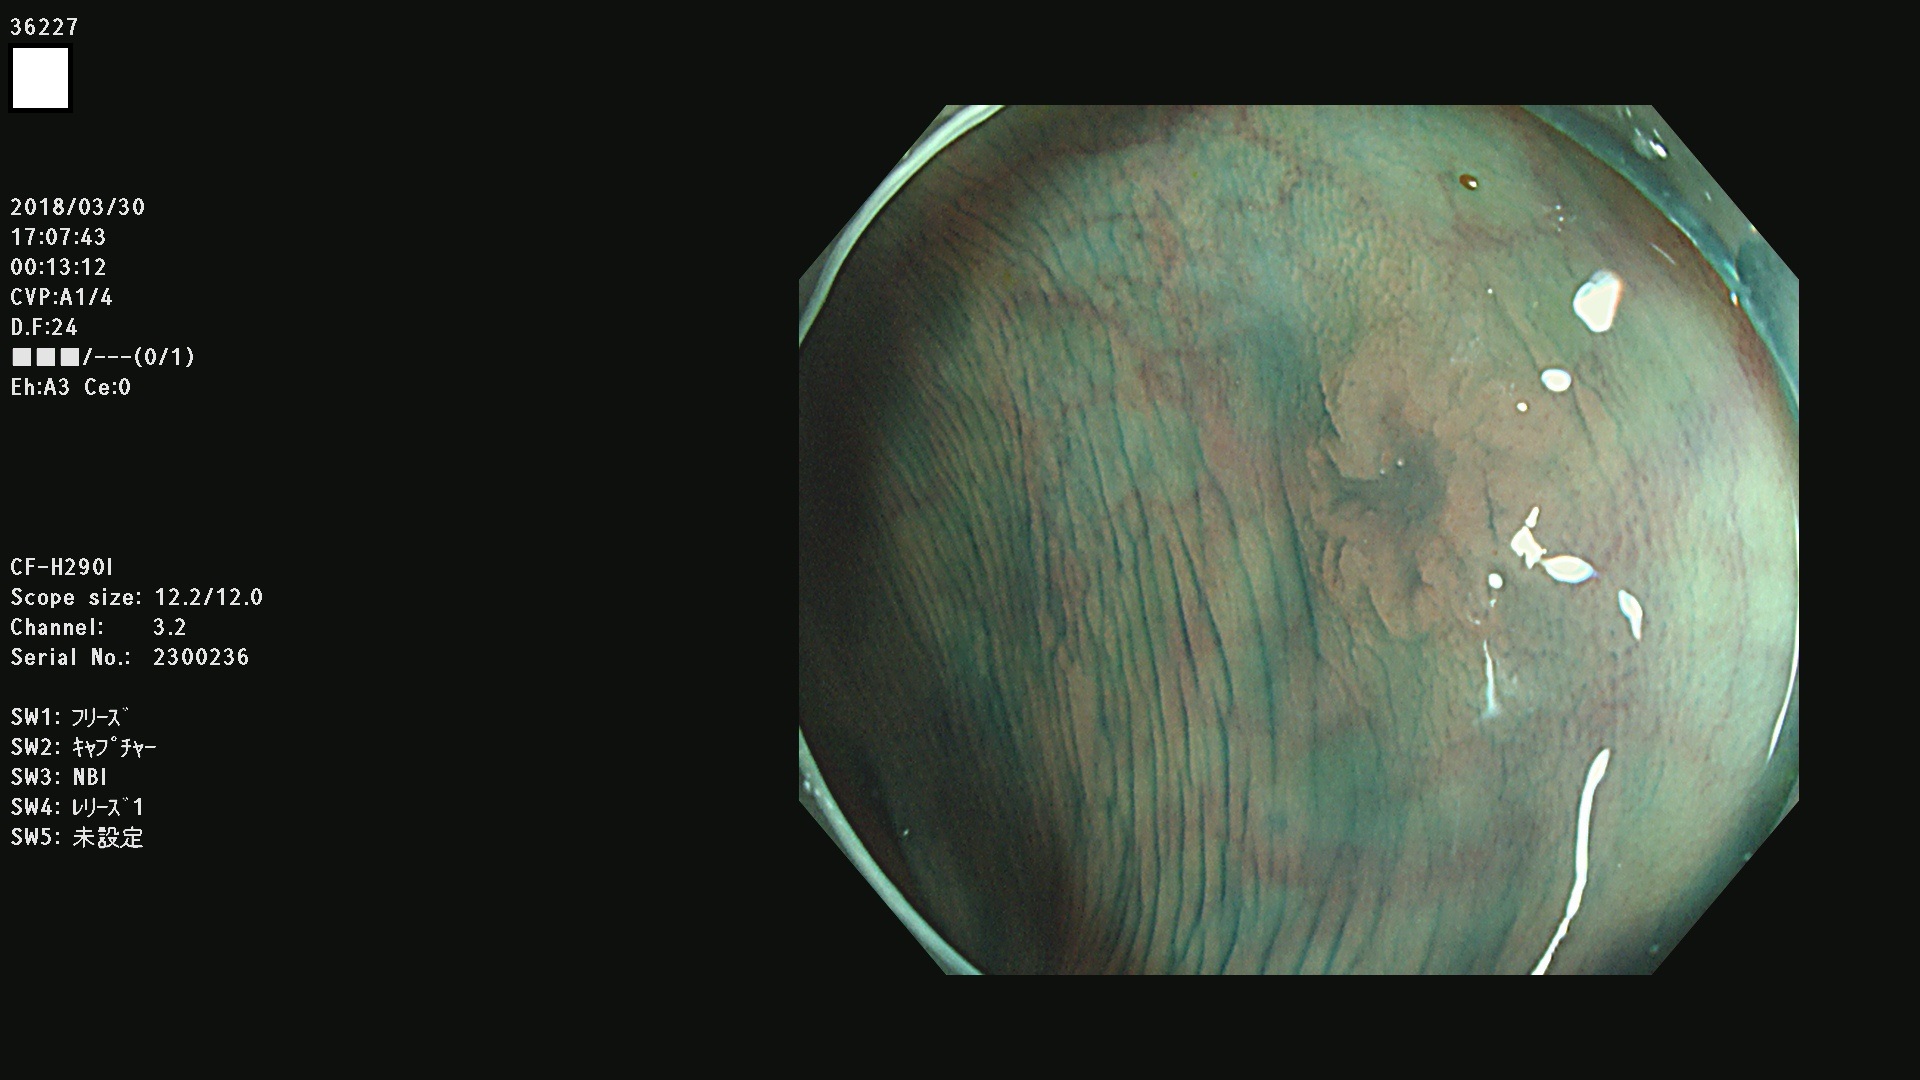

発見困難で危険性の高い平坦型病変(上記100名より抽出)

36201 36202 36203 36205 36207 36209 36210 36212 36213 36214 36215 36217 36220 36221 36222 36224 36225 36226 36227 36229 36230 36231 36232 36235 36236 36238 36240 36243 36244 36246 36247(SSAPのみ。SPS) 36248 36249 36251 36252 36253 36254 36255 36256 36257 36258 36259 36261 36262 36264 36265 36267 36269 36270 36272 36274 36275 36276 36279 36280 36281 36283 36285 36288 36289 36291 36292 36295 36296 36297 36299